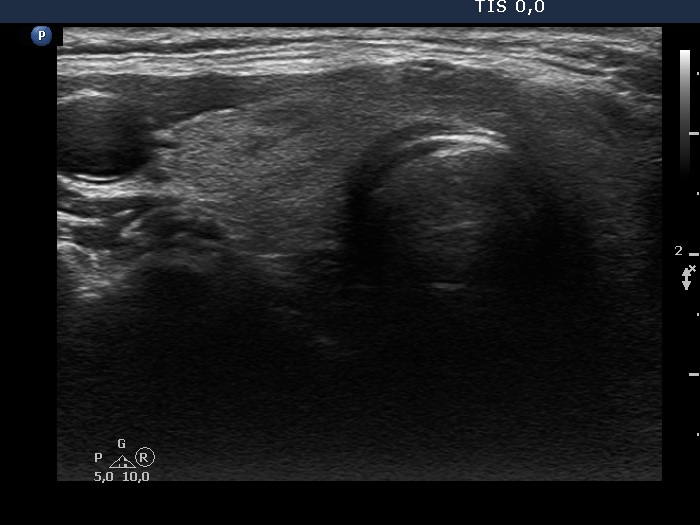

Ultrasonography. The thyroid was echonormal and had tiny, moderately hypoechoic areas. The echogenicity index was around 10%. There was a dominantly hypoechoic, heterogeneous nodule in the left lobe. The lesion presented various echogenic figures, including microcalcifications and amorphous hyperechoic patches.